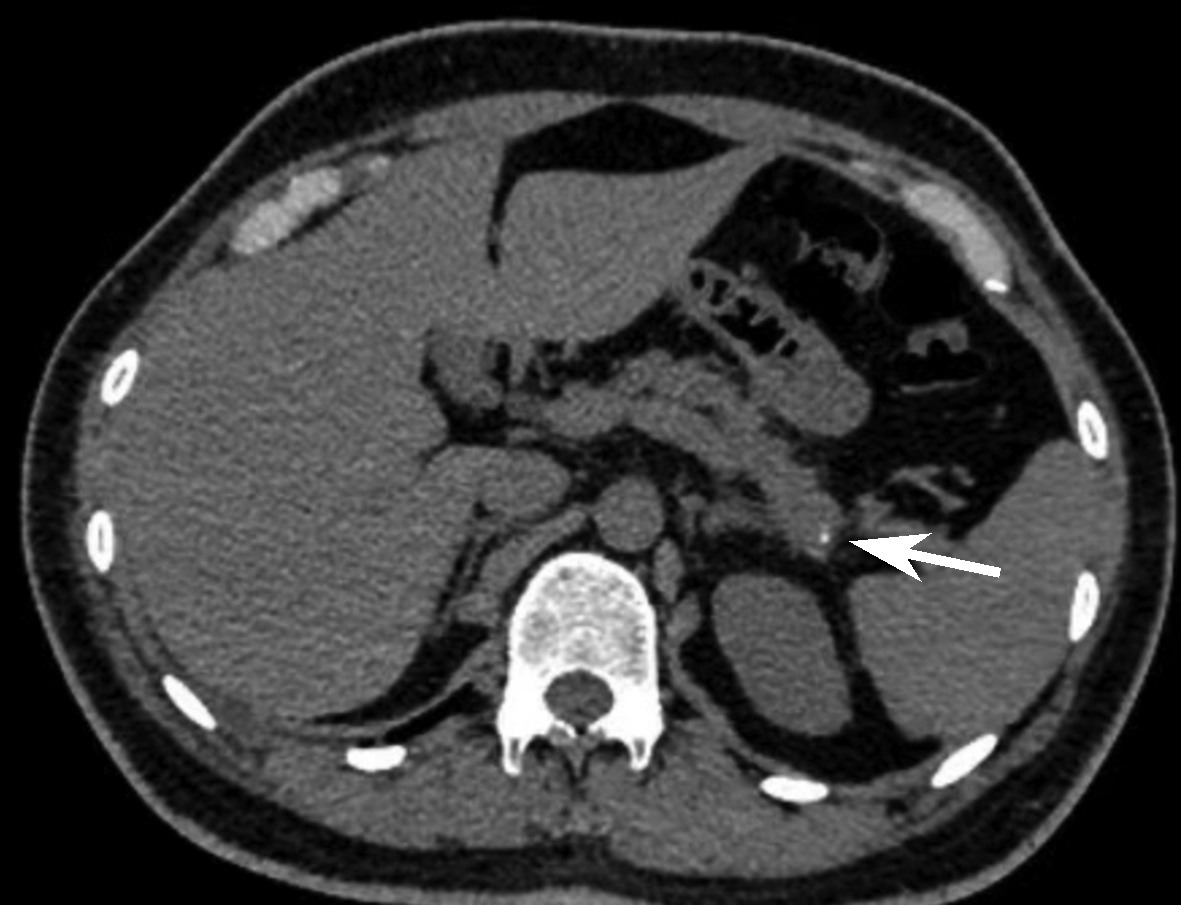

胰管结石治疗方案的选择分析与比较

摘要:

目的  收集并对比分析内镜逆行胰胆管造影(ERCP)、腹腔镜术和开腹手术三种方案治疗胰管结石(PDS)患者的临床资料及治疗效果,总结PDS治疗方案选择的经验,进一步研究探讨可行的使患者获益最大化、最优化的治疗方案。  方法  回顾性分析2014年6月—2018年12月海军军医大学附属公利医院治疗的131例PDS患者的临床资料。根据手术情况分为3组:ERCP组69例,腔镜组32例,开腹组30例。监测3组患者手术前后相关指标的变化;进一步对比分析腔镜组和开腹组的手术疗效。正态分布的计量资料两组间比较采用独立样本t检验;多组间比较采用单因素方差分析,进一步两两比较采用LSD-t检验或SNK-q检验。偏态分布的计量资料两组间比较采用Mann-Whitney U检验,多组间比较采用Kruskal-Wallis H检验。手术前后相关指标差异比较采用重复测量资料的方差分析和Friedman检验。计数资料组间比较采用χ2检验。  结果  131例PDS患者中Ⅰ型40例、Ⅱ型76例、Ⅲ型15例。腔镜组与开腹组主要手术方式的病例数比较差异无统计学意义(χ2=1.93,P>0.05)。腔镜组和开腹组血WBC、CRP、PCT、HOMA-IR在手术前后的动态变化存在明显差异(F=24.68、χ2=227.66、F=45.37、F=106.71,P值均<0.05)。腔镜组手术时长、术中出血量、术后首次排气时间、术后止痛药物应用频次、腹腔引流管拔除时间、术后近期并发症、术后平均住院时长等观察指标均较开腹组明显减少/缩短(t=-4.80、t=-9.43、Z=-6.78、t=-11.59、Z=-6.77、χ2=9.24、t=-3.60,P值均<0.05)。ERCP组、腔镜组、开腹组术后近期并发症发生率分别为24.64%、28.13%、66.67%,差异有统计学意义(χ2=17.12,P<0.05);ERCP组及腔镜组术后近期并发症发生率均显著低于开腹组(χ2值分别为15.78、9.24,P值分别为<0.05、0.02)。ERCP组、腔镜组、开腹组治疗有效率分别为91.30%、93.75%、73.33%,3组间有效率差异有统计学意义(χ2=7.70,P=0.02),ERCP组及腔镜组有效率均好于开腹组(χ2值分别为5.56、4.77,P值分别为0.02、0.03)。  结论  ERCP为临床微创治疗部分Ⅰ、Ⅱ型PDS的首选治疗方法,安全有效、严重并发症少。外科手术是治疗复杂型PDS的重要手段,但技术复杂、操作难度大。腹腔镜术较开腹术创伤小、严重并发症少,腹痛缓解率高,可以显著减少手术时长、降低术中出血量及缩短术后平均住院时长。针对复杂型PDS宜优先选择腹腔镜术治疗。